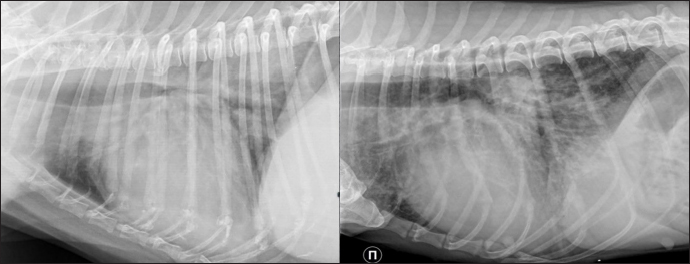

Clinical signs included progressing dyspnea, acute dyspnea, chronic cough, weakness, lameness, cyanosis, and syncope. Chest radiographs obtained on the day of presentation with symptoms showed a diffuse interstitial unstructured pattern with loci of alveolar pattern, cardiomegaly, and in some cases, with left atrial enlargement (Fig. 1).

Fig. 1. Lateral thoracic radiographs of 2 dogs. Left one—RHF group, right -sPCH. Both presented with unstructured interstitial and local alveolar patterns.